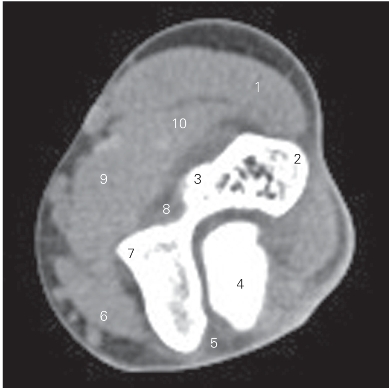

图4-28 经肘关节上份的横断层CT图像(软组织窗)

1 旋前圆肌 pronator teres 2 肱骨内上髁 medial epicondyle

3 肱骨滑车 trochlea of humerus 4 尺骨鹰嘴 ulnar olecranon

5 肘肌 anconeus

6 桡侧腕长、短伸肌 extensor carpi radialis longus and brevis

7 肱骨小头 capitulum of humerus 8 冠突窝 fossea coronidea

9 肱桡肌 brachioradialis 10 肱肌 brachialis